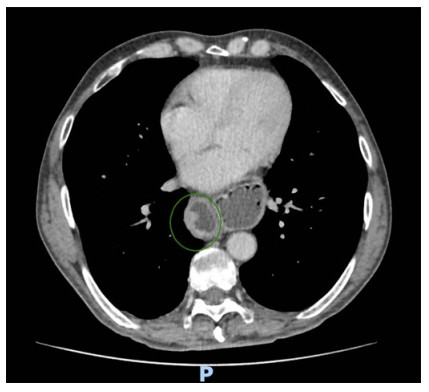

Abstract: Hiatal hernia is a rare postoperative complication of esophagectomy in the treatment of esophageal cancer. Although rare, its incidence increased after the establishment of minimally invasive surgical techniques. The patient is usually oligosymptomatic, and the diagnosis is made in the late postoperative period, during outpatient follow-up. The initial presentation of hiatus hernia with hemodynamic instability is a rare condition that has never been described in the literature before. In the following report, we address the clinical picture, diagnosis, and treatment for this condition, discussing the main nuances of the literature.